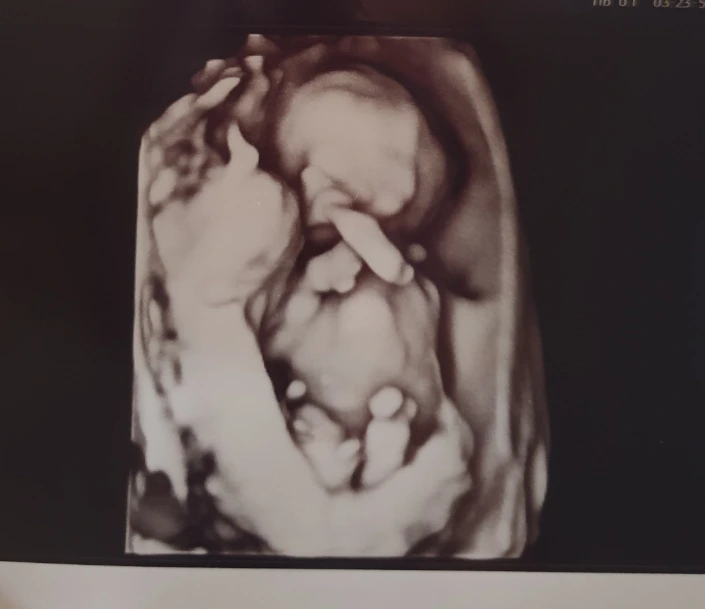

이 시기에 무료 입체 초음파도 같이 진행했는데 늘 보던 초음파와 달리 형체가 뚜렷하게 보여서 너무 신기했다.

흑백으로 진행되는 게 아쉬웠지만 그래도 앞모습을 보여줘서 너무 고마웠다. 귀엽게 손을 크로쓰 하고 있는 우리 아기, 남편은 웃으면서 뱃속에서 벌써부터 칼싸움하듯이 놀고 있는 건가?라고 했다 ㅎㅎ 초음파상에서 엄청 활발하다던데 아직 태동은 느껴지지 않았다.

이 날 우리는 성별도 알게 되었. 진료를 보기 전 입체 초음파를 봐주는 분이 무언가가 보인다고 하셨다. 그리고 진료를 봤는데, 선생님도 '여기 뭐가 있네요~'라고 힌트 아닌 힌트를 주셨다. 성별을 알고 나니 기분이 묘했다. 나와 다른 성별이라서 걱정도 되고, 어떻게 키워야지 벌써부터 겁도 났다. 하지만 걱정 사이로 기대감이라는 감정도 슬며시 고개를 들었다.